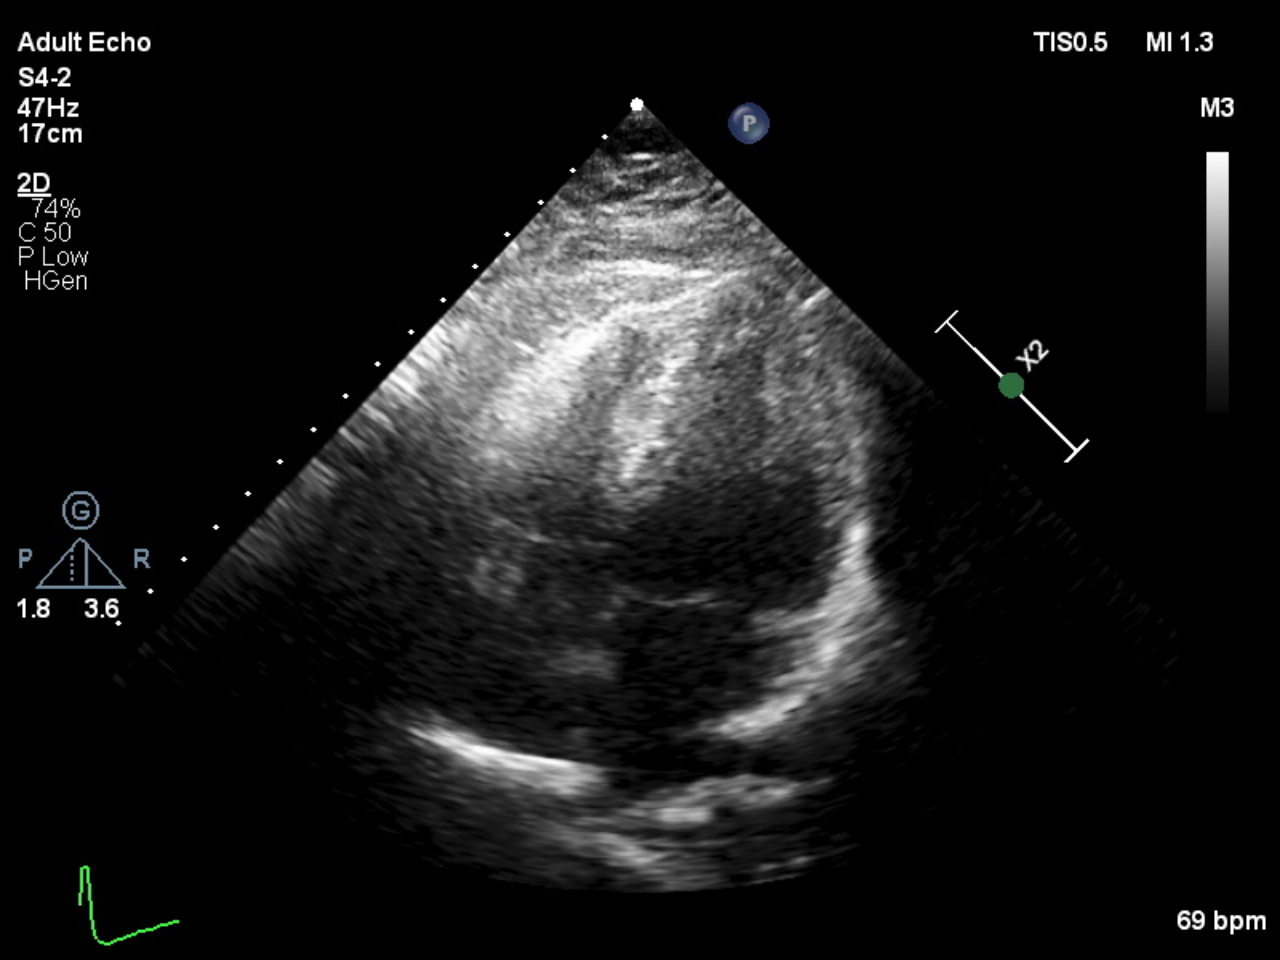

Electrocardiogram: ST elevation in aVR and V1 with widespread ST depressionEchocardiography: EF 60.4% with anteroseptal hypokinesia. No significant valvular abnormalities.